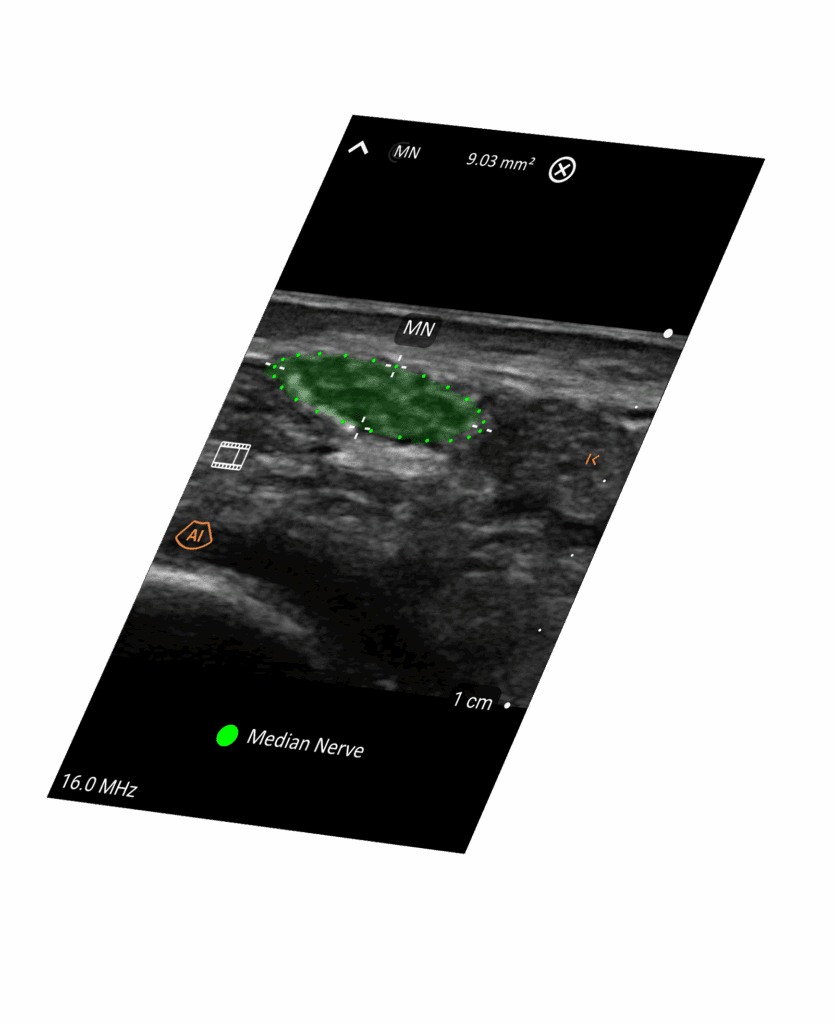

IA pour Rationaliser

Accélérez les workflows avec l'automatisation intelligente et le guidage des aiguilles.

Clarius Intelligence combine des outils intelligents et l'automatisation pour rationaliser le balayage et vous permettre de rester concentré sur votre patient.